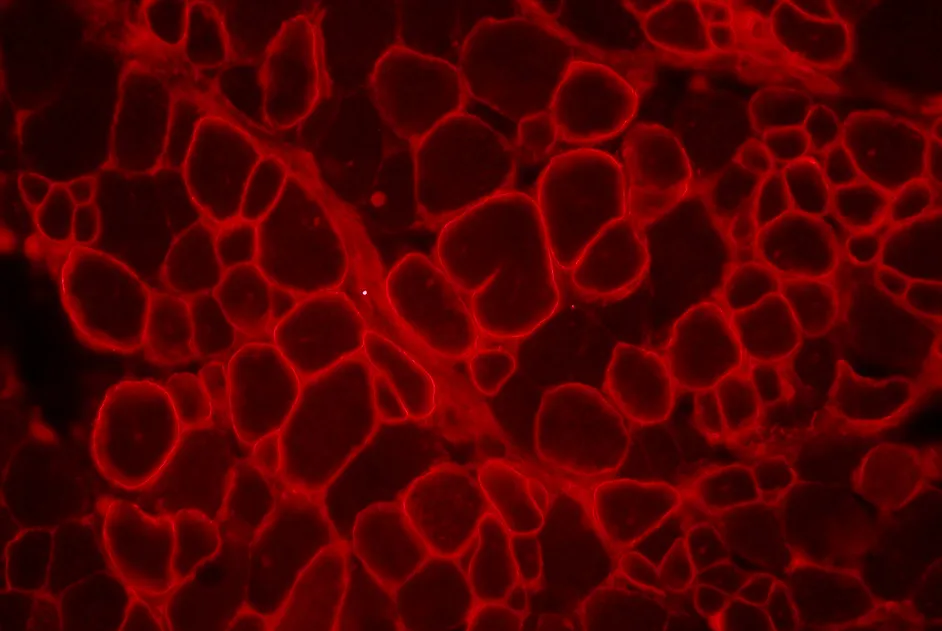

Mise en évidence d’une interaction de la mitsugumine 53 avec la pompe à calcium, SERCA1, qui diminuerait l’activité de SERCA1.